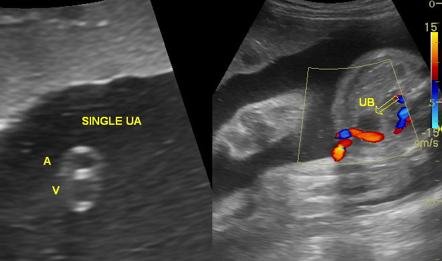

hình ảnh dây rốn bình thường

Hình ảnh dây rốn bình thường: 1 tĩnh mạch lớn (màu xanh) và 2 động mạch nhỏ (màu đỏ)

hình ảnh dây rốn 2 mạch máu

Hình ảnh dây rốn 2 mạch máu: 1 động mạch, 1 tĩnh mạch